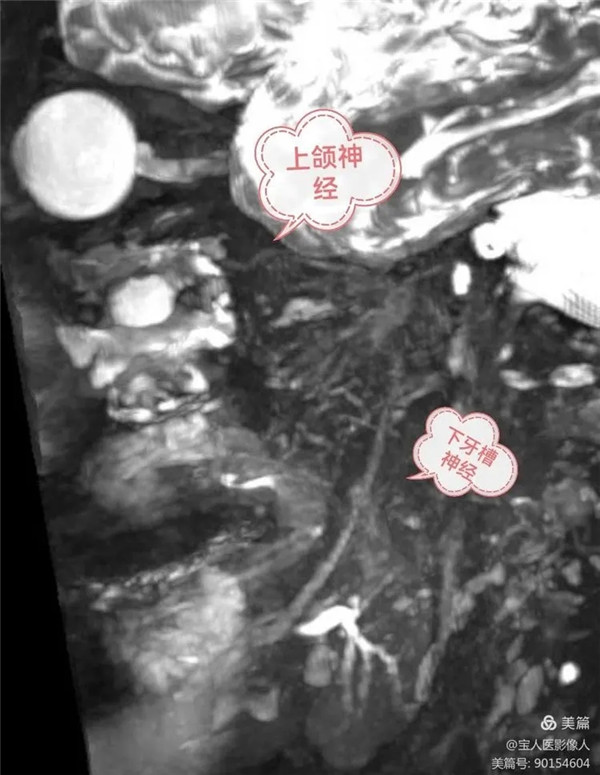

磁共振成像側位圖,同時顯示上頜神經,下牙槽神經

上頜神經自三叉神經節發出后,立即進入海綿竇外側壁,之后經圓孔出顱,進入翼腭窩,再經眶下裂入眶,續為眶下神經。上頜神經分支分布于上頜各牙、牙齦、上頜竇、鼻腔和口腔的粘膜以及瞼裂間的面部皮膚以及部分硬腦膜。

(4) 下牙槽神經為混合神經,下牙槽神經在舌神經的后方,沿翼內肌的外側面下行,一般軀體感覺纖維經下頜孔入下頜管。在下頜管內分支構成下牙叢,分支分布于下頜各牙和牙齦。